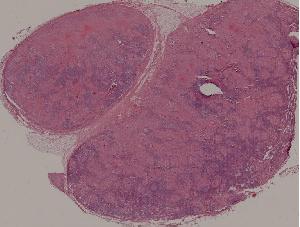

75.慢性硬化性肾小球肾炎

76.急性肾盂肾炎

77.慢性肾盂肾炎

41.肺机会性感染

71.急性肾移植排异反应

72.狼疮性肾炎

36.恶性淋巴瘤

80.乳腺浸润性导管癌

84.Graves病

93.流行性脑脊髓膜炎

94.乙型脑炎

88.慢性纤维空洞性肺结核

89.淋巴结结核

90.皮肤瘤型麻风

91.结核样性麻风

92.肠伤寒

95.脊髓灰质炎

96.肺曲菌病

97.结肠阿米巴病

98.结肠血吸虫病